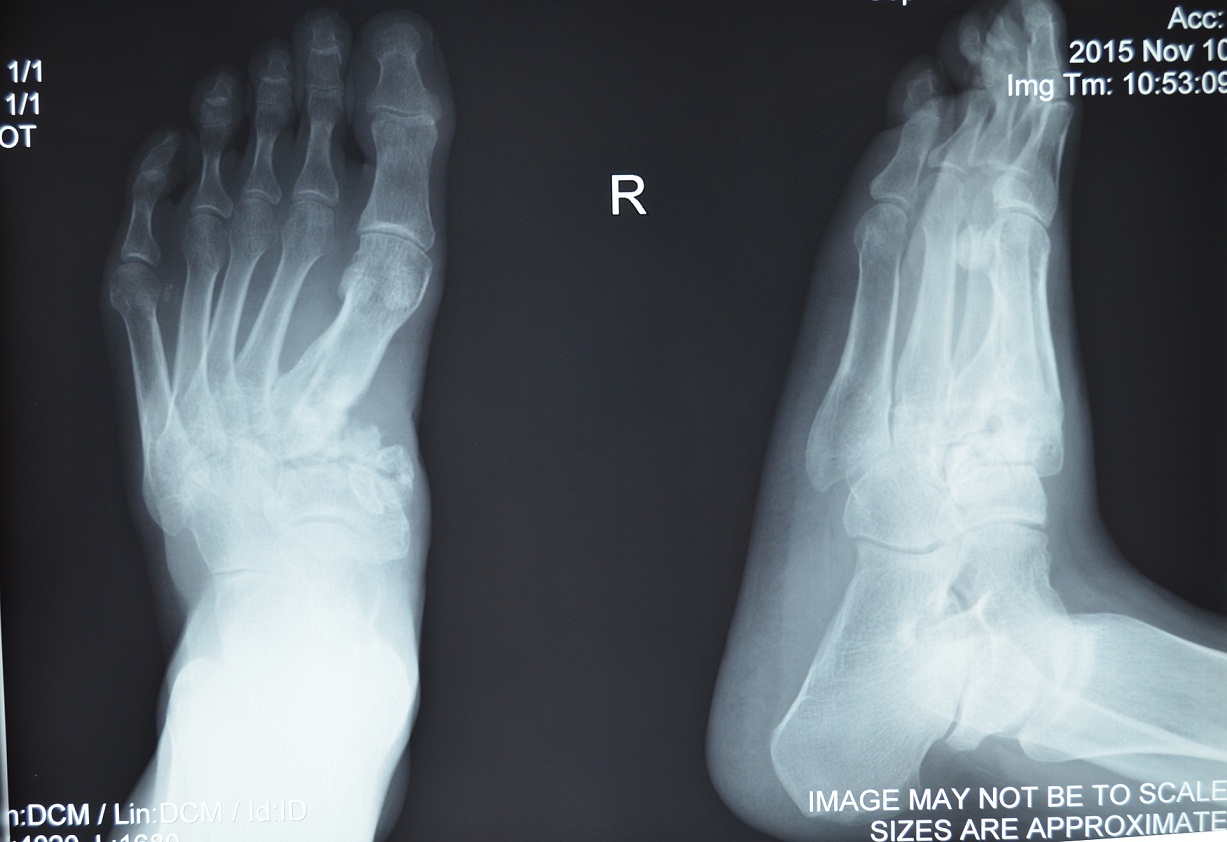

"Бійців з різних куточків України знаходимо самостійно через соціальні мережі або їх на лікування в клініку приводять волонтери", – розповідає координатор проекту "Біотех-реабілітація поранених" і співробітник клініки Станіслав Кушнаров. Далі боєць або попередньо присилає рентгенівські фото, чи одразу приїздить на діагностику. Тут уже лікарі дивляться: якщо це "їхній випадок" і вони можуть допомогти – прописують схему лікування, визначаються з тим, які будуть затрати, а потім це узгоджується з "Народним проектом". У фонді ж, у свою чергу, вирішують, чи зможуть взяти бійця під опіку, і далі проект уже починає збір грошей. Причому чим менше часу минає з моменту поранення бійця, тим лікування ефективніше й дешевше. Адже бойові рани вважаються первинно інфікованими, в них розвивається остеомієліт. Коли поранення задавнені, починається некроз кістки, вона сильніше руйнується, а також "гаситься" імунітет, який потім лікарям доводиться "розкачувати", бо він просто життєво необхідний у такому лікуванні.

Ось і нині на лікуванні у клініці перебувало двоє бійців АТО, з якими вдалося поспілкуватися. Цього разу вони пробули тут близько тижня і отримати потрібні процедури. Перший – це 38-річний прикордонник Сергій із Харкова, який зазнав вогнепального поранення гомілки під Іловайськом на Донеччині, та 27-річний Олександр, боєць 1-го батальйону 30-ї механізованої бригади, який отримав осколкове поранення стопи зі зміщенням кісток у селі Червона Поляна неподалік від Лутугиного на Луганщині. Обоє були поранені ще у 2014 році.

Другий боєць, Олександр, у 2014-му отримав осколкове поранення стопи зі зміщенням кісток. Перебиті були перша, друга і третя передплюсні кістки в ступні – вони фактично "стояли одна на одній". Чоловіка лікували в Харкові, у Вінниці, в Житомирі. Він згадує: "Було проблематично взуватися, ну і ходити не можна було. Тільки кілометр-півтора пройти міг, потім береш палку, ще трохи пройшов і вже береш другу палку, а потім дуже сильно боліло. А ще я взутись не міг: у мене такий горб був. Виходить, береш кросівки на розмір більше, розшнуровуєш їх, щоб нормально було взутись. У клініці мені кістки поставили на свої місця та зафіксували шпицями".

Нині кістка для Олександра вже вирощена. "Зараз підготовка йде, прокапають, і в мене вже кістка готова для трансплантації. Ця пересаджена кістка закриє той простір у ступні", – розповів боєць. На запитання, чого чекає від операції – відповідає не замислюючись: "Хочу чимскоріше ходити, літо он іде, треба гроші заробляти. Боліти, мабуть, все одно буде, але так, щоб можна було працювати і чимось займатись".